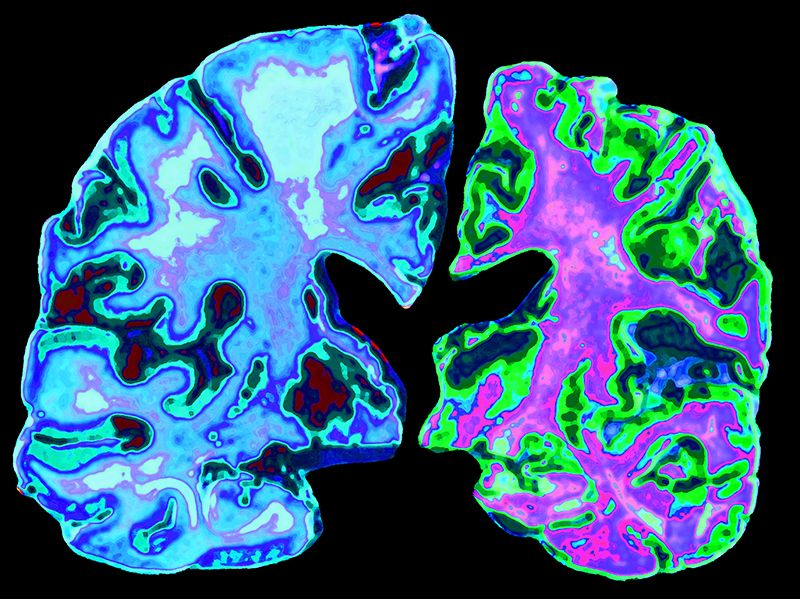

Однією із проблем є виявлення початку розвитку хвороби, адже чим раніше почати лікування, тим повільніше патологія буде розвиватися, а людина проживе довше та краще (ми поки не в змозі вилікувати ці хвороби). Дослідники взяли результати сканування головного мозку 3688 людей різного віку та побудували на основі комп’ютерних нейромереж математичну модель зв’язку будови мозку та віку. Далі вони застосували розроблений алгоритм до сканів мозку людей із деменцією. Виявилося, що чим більшою була різниця між обчисленим та реальним віком, то більшою була ймовірність коректної діагностики деменції. Автори зазначають, що цей параметр може бути непоганим біомаркером для виявлення початку розвитку даної хвороби. Цікаво, що поміж різних нервових структур найбільший внесок у діагностику віку вносила щільність сірої речовини у гіпокампі та амигдалі (структурі, яка пов’язана із регуляцією емоцій).

Джерело: Wang J, Knol MJ, Tiulpin A, Dubost F, de Bruijne M, Vernooij MW, Adams HHH, Ikram MA, Niessen WJ, Roshchupkin GV. Gray Matter Age Prediction as a Biomarker for Risk of Dementia. Proc Natl Acad Sci U S A. 2019 Oct 15;116(42):21213-21218. doi: 10.1073/pnas.1902376116